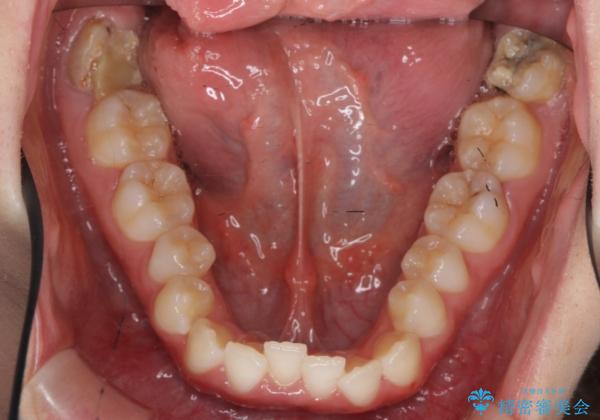

下の歯のがたつき 上より気になる

下の歯のがたつきが上よりも多い状態でした。

下の前歯は上の歯の内側にあるため、外に並べることができないため、上ほど簡単ではありません。

すき間をしっかりとって並べる必要があります。

今回は、下の歯を健康に支障が出ない範囲でわずかに削合し、並べるようにしました。(ディスキングといいます)

下の親知らずは虫歯になっていたため矯正前に抜歯しています。